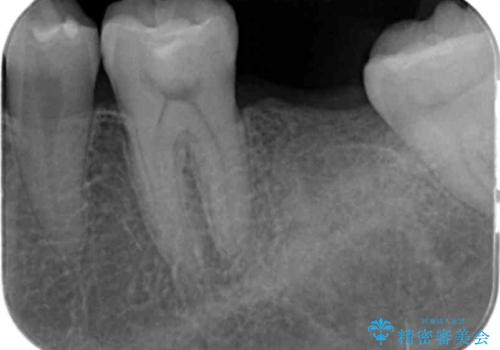

- 奥歯が割れたあと、他院で抜歯したところにインプラントを希望して来院。2回法で行いました。

奥歯を抜いたまま放置すると後方の歯が前に倒れこんでしまい、かみ合わせやその後の治療に支障がでます。早めに処置することをおすすめします。

- 外科手術のため、術後に痛みや腫れ、違和感を伴います

- メンテナンスを怠ったり喫煙により、お口の中に大きな悪影響を及ぼすインプラント周囲炎等にかかる可能性があります

- 糖尿病、肝硬変、心臓病等の場合、インプラント治療ができない可能性があります

- 高血圧、貧血・不整脈等の場合、インプラント治療後に治癒不全を招く可能性があります